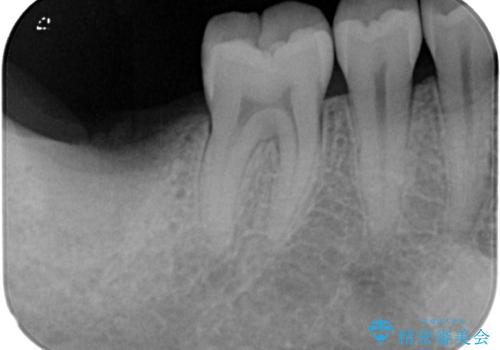

来院時には抜歯して1ヶ月ほど経過していたとのことで、3次元レントゲンよりインプラントの早期埋入が可能と診断されました。

抜歯された骨の穴は、インプラント埋入時にはまだ大きな窩洞となっていましたが、径の大きいワイドインプラントを選択することで、埋入時に十分な安定を獲得することができました。

後方には欠損が残っていたため、補填材を填入しました。